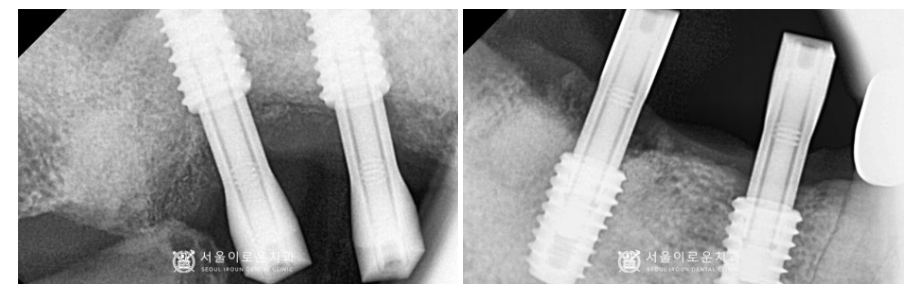

술 후 파노라마와 3D-CT를 통해

발치 후 즉시 임플란트와

상악동 거상술을 동반한 임플란트가

안정적으로 식립된 것을 체크하였답니다.